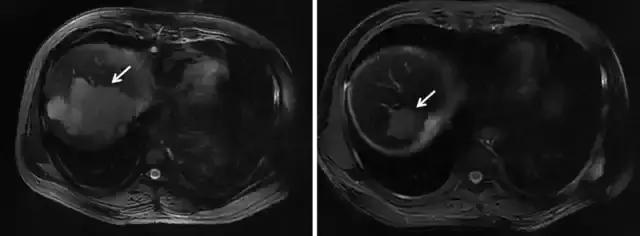

2018年国际放疗专业期刊发表了关于早期肝癌SBRT的综述性文章,纳入分析721个病灶(642名患者),结果显示,原发性肝癌SBRT治疗后3年局部控制率高达86%。研究也显示小肝癌不宜手术切除者,SBRT与射频消融一样,可作为不能手术的肝癌的替代治疗手段。2016年JCO(临床肿瘤学杂志)报道显示,224例早期肝癌分别接受射频消融(RFA)或者立体定向放疗(SBRT),结果显示,2年局部控制率分别为RFA 80%,SBRT 84%。且随着肿瘤体积增大,RFA治疗后局部复发风险逐渐提高,而SBRT无明显改变。对于>2cm的肝癌,SBRT的局部控制率明显优于RFA(图1)。

图1 SBRT治疗前后病灶变化明显(病灶如箭头所示,SBRT后肿瘤完全消失)。